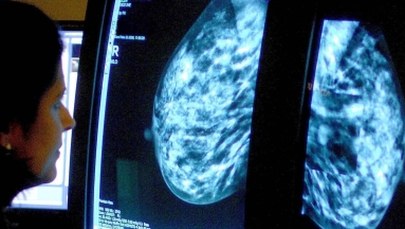

Dwie pierwsze pacjentki z mutacjami genów predysponującymi do zachorowania na raka piersi poddały się w Białostockim Centrum Onkologii (BCO) zabiegom tzw. profilaktycznej mastektomii, czyli usunięcia piersi. Zabiegi te są już refundowane przez NFZ.

Profilaktyczne mastektomie to są zabiegi, które zmniejszają w sposób istotny ryzyko zachorowania na raka piersi. Rozporządzenie ws. refundacji zabiegów (mastektomii z rekonstrukcją piersi) minister zdrowia wydał w styczniu 2019 r.

Patomorfolog dr hab. Luiza Kańczuga-Koda dodała, że szacuje się, że ryzyko zachorowania na raka piersi przy obciążeniu genetycznym - zwłaszcza mutacją genów BRCA1 i BRCA2 wynosi nawet do ok. 80 proc. Również wzrasta ryzyko raka jajnika, raka otrzewnej i raka jajowodu - mówiła Kańczuga-Koda. Zaznaczyła, że kobiety obciążone mutacjami BRCA1 i BRCA2 to osoby młode, przed 40. rokiem życia, nowotwór jest też agresywny.